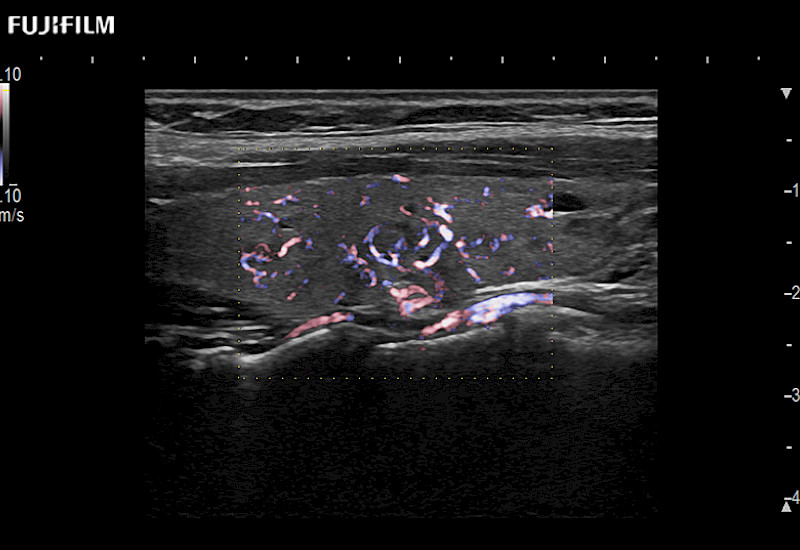

The ARIETTA 750 incorporates all of the proven technologies and functions that medical professionals have come to expect from Fujifilm Healthcare.

ARIETTA 750 is the definitive diagnostic ultrasound solution for any clinical setting - Private Office, Imaging Center, or Hospital. The ARIETTA platform provides the ultimate in clinical performance with its state-of-the-art features and large user-friendly display.

The ARIETTA 650 DI combines trusted Fujifilm Healthcare technologies and features tailored for surgical oncology.

Designed to meet the demands of surgeons, the ARIETTA 650 DI offers precise guidance. Its advanced capabilities and large, intuitive display offer accurate and efficient care in operating rooms and specialized surgical settings.